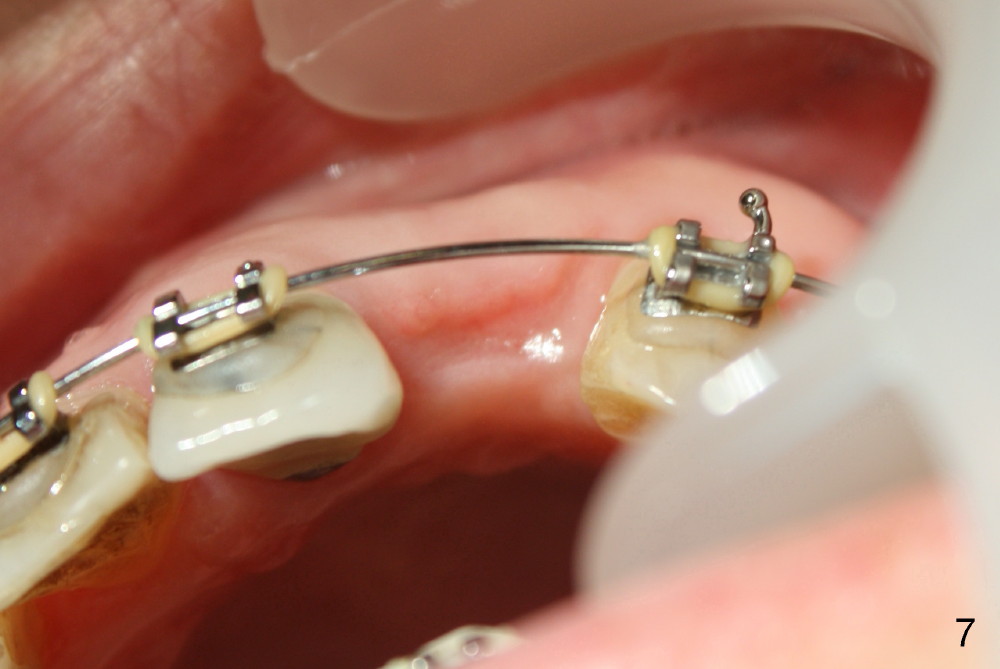

A prominent feature of implant failure in this case is pain. The patient feels that the pain is from the base of the nose. PA taken 3 days postop shows that the implant is inferior to the nasal floor (Fig.2 red ^). Clinically, the buccal gingiva continues to be erythematous 10 days postop (Fig.1). The pain is so unbearable that the implant (3.8x14 mm) is removed 10 days post placement. After repeated debridement, a 4.1 mm tap (Fig.3 T) is manually inserted with torque. A 4.1x14 mm submerged implant is placed with insertion torque < 30 Ncm, but it is placed subcrestally (Fig.4 <--). This time an immediate provisional is not provided. The flap is sutured. The pain disappears immediately. No infection is found 7 days postop (Fig.5). However, an asymptomatic vesicle is noted at the crest 3 weeks postop (Fig.6). The gingiva looks normal 2 and 3 months postop (Fig.7,8). The coronal gap dissolves 3 months postop (Fig.9 >, as compared to Fig.4), suggesting osteointegration. The implant is uncovered 4 months postop (Fig.10). Bracket is placed 5 months postop (Fig.10'). One month later, the left central incisor improves in position coronocervically (Fig.11), but the overjet needs correction by distalization of the upper anterior teeth. The implant at the site of #10 may be used as an anchorage.